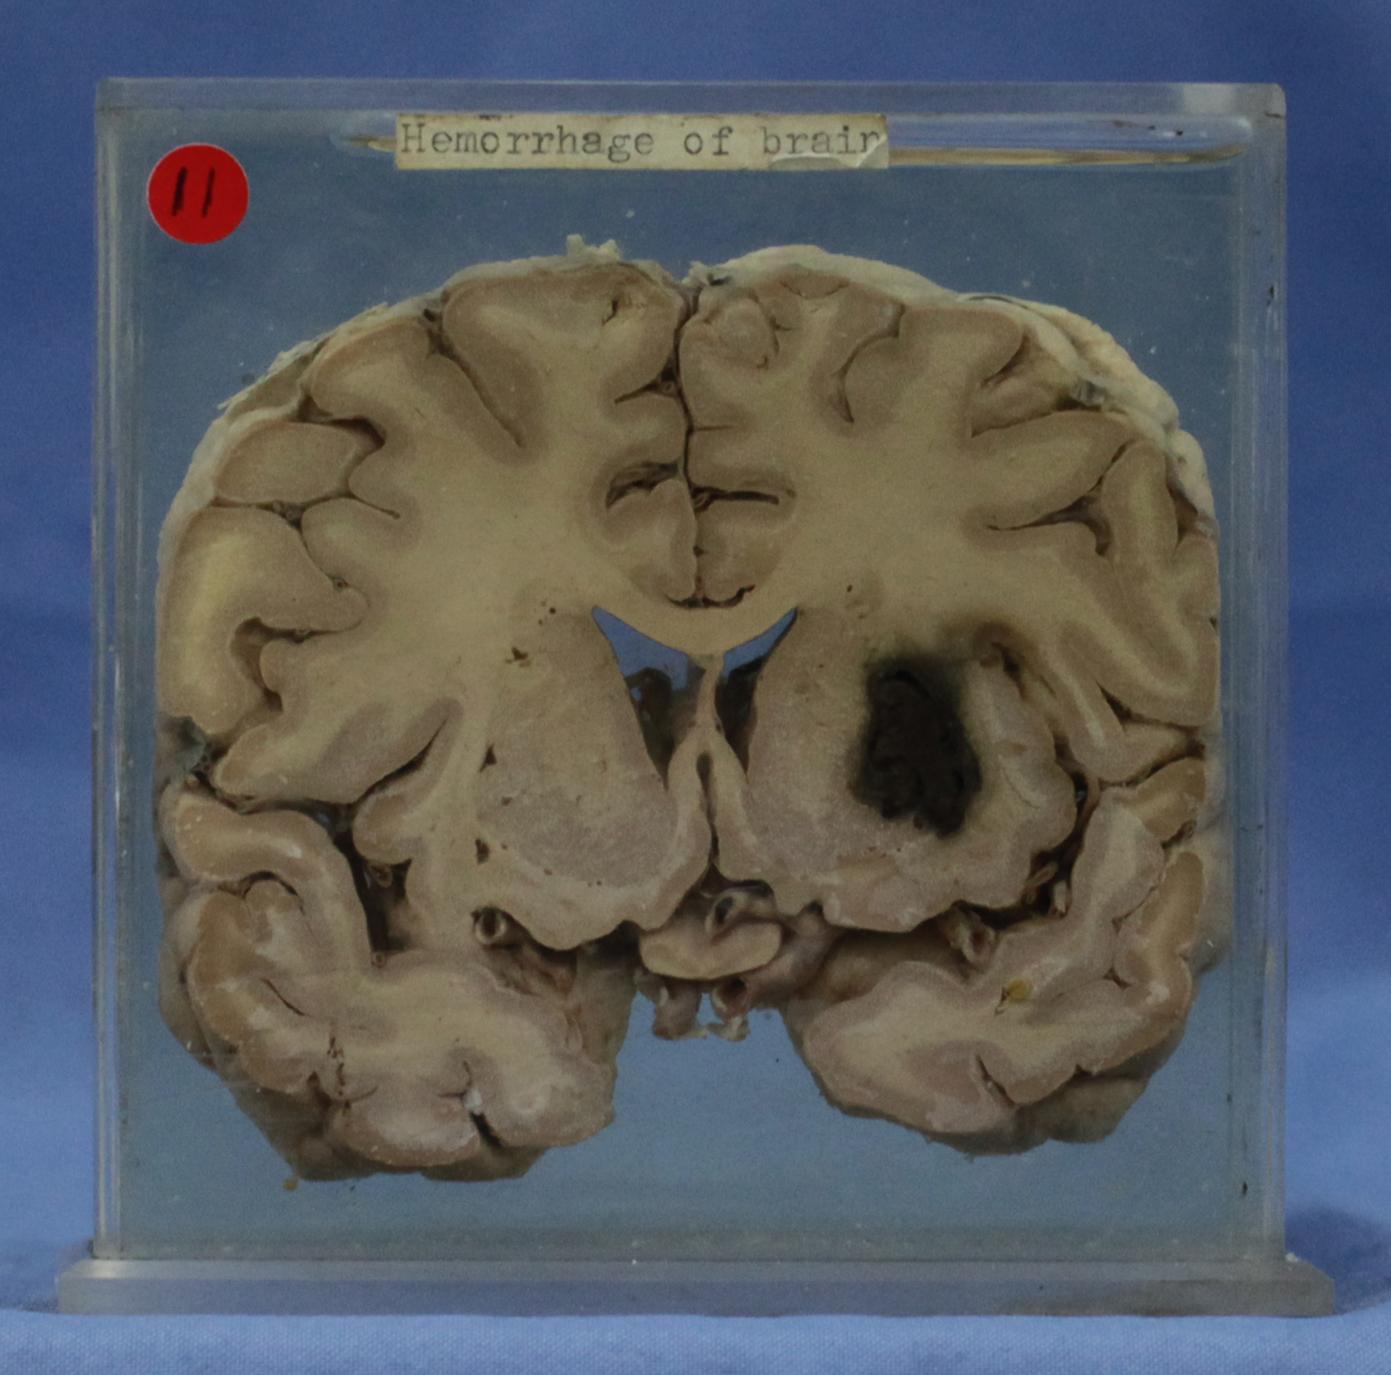

神经疾病-58-11. 基底动脉粥样硬化,左侧基底节外侧陈旧性梗死灶

经丘脑水平的脑水平切块,切块见丘脑外侧的基底核外侧凝血块直径2-3cm,并有含铁血黄素着色,局部组织破坏,同侧侧脑室变窄,基底面见硬化的动脉开口,切面口径变小,管壁见灰黄斑块。